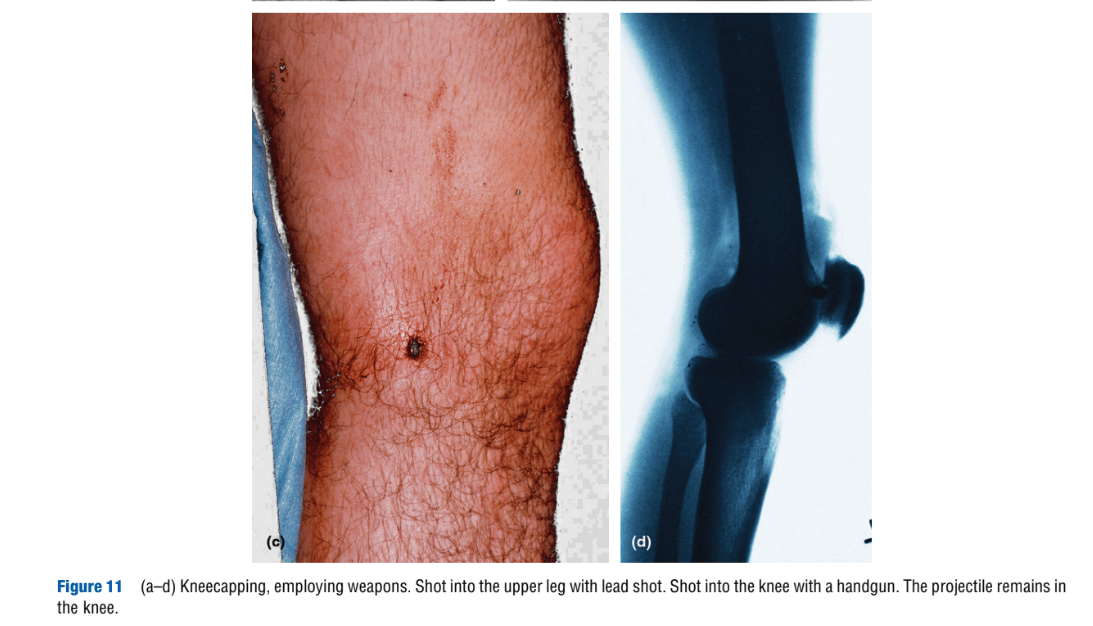

“Torture,” by H. Vogel. Encyclopedia of Forensic Sciences, second edition. 2013.